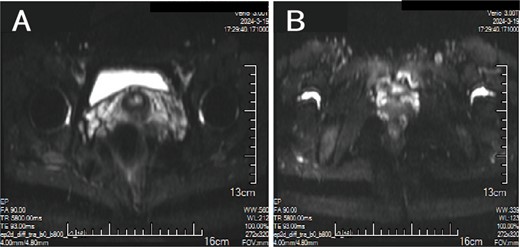

A 38-year-old married female patient presented with a lump near her anus 10 years ago, without apparent cause or symptoms such as redness, swelling, heat, or pain, nor cough, abdominal pain, or diarrhea. No specific treatment was administered. The patient now reports that the lump has grown larger and is accompanied by increasing swelling and discomfort. Seeking further diagnosis and treatment, she visited our outpatient department, where she was admitted with the condition “perianal lump.” Physical examination revealed a body temperature of 36.5°C, pulse rate of 86 beats/min, respiratory rate of 19 beats/min, and a blood pressure of 134/85 mmHg. Admission symptoms include perianal swelling and pain, with itching; no signs of fever, chills, rupture, or pus discharge; bowel movements once or twice daily, and normal urination. The patient has one child and underwent a lateral epidural resection 12 years ago due to natural childbirth. Specialist examination revealed a 4-cm lump with a hard texture at 7–11 o’clock next to the anus, and a radial surgical incision at the 7 o’clock anal margin. Digital rectal examination found no lump, depression, or induration in the anus, and no blood on fingertips. The initial diagnosis was a perianal lump. Auxiliary examinations included ultrasound, which revealed a 4-cm lump in the subcutaneous soft tissue near the anus with minor blood flow signals within and around it, suggestive of an inflammatory lesion (Fig. 1A and B); and pelvic MRI, which suggested a left perianal lump consistent with a perianal abscess (Fig. 2A and B). Under spinal anesthesia, the perianal lump was removed, and postoperative pathology confirmed the presence of endometriosis (Fig. 3).

MRI: (A, B) A cluster of low/high mixed signals such as T1 and T2 can be seen on the left side of the anus, and the DWI signal is partially increased.

PE represents a specific type of endometriosis, with related studies reporting that iatrogenic implantation is closely linked to the development of endometriotic lesions in perineal lateral incision scars [6]. PE exhibits symptoms similar to those of perianal abscesses, with both conditions originating around the anus. These conditions are clinically rare, often leading to misdiagnosis due to a lack of understanding among clinicians. In contrast to perianal abscesses, PE typically presents as recurrent perianal masses accompanied by cyclical pain, with the masses enlarging during menstruation and subsequently shrinking or disappearing thereafter [7, 8]. Patients often have a history of perineal lacerations or episiotomy, with surgical scars typically visible on specialized examinations. Anorectal examinations reveal no signs of anal sinus infection [9]. Ultrasonography demonstrates heterogeneous hypoechoic masses with punctuate or branching blood flow signals [10]. MRI exhibits a sensitivity of 90%–92% and a specificity of 91%–98% for the diagnosis of PE. MRI not only precisely locates the lesion but also outlines its extent, enabling differentiation from various anorectal conditions, thereby greatly aiding in the disease’s diagnosis [11]. Histopathological examination serves as the definitive diagnostic method for this condition, requiring the microscopic identification of two out of three components: endometrial stromal cells, glands, and hemosiderin, to confirm the diagnosis [12].